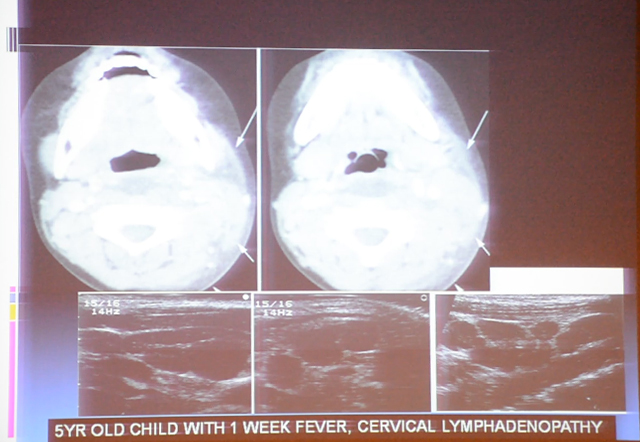

APIRIA 2016